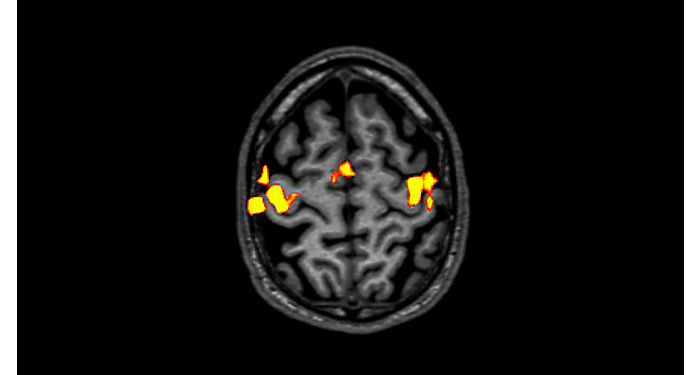

70% of radiologists consider neuro indications to be challenging, mostly due to a lack of appropriate imaging and visualization techniques¹. Philips aims to provide the best possible diagnostic clarity and treatment guidance for all patients with neurological disorders. By leveraging our dStream digital platform, this year, we are introducing, a set of novel imaging and visualization strategies. These may empower you to resolve complex neuro questions with more certainty, as well as unlock new neuro territories in advanced Neurofunctional applications. This is a key step towards elevating neuro diagnostics and ultimately touching more lives with MR imaging. ¹ TMTG Market Survey 2016

New neuro applications